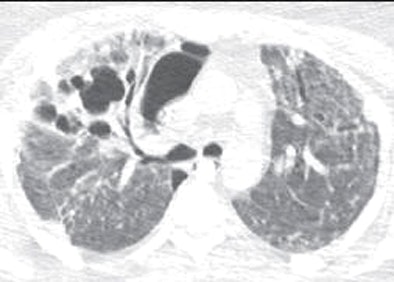

| Thirty-three-year-old woman with laboratory-confirmed S-OIV (H1N1) requiring extracorporeal life support. Pseudomonas infection was confirmed on subsequent bronchoalveolar lavage. Follow-up CT 41 days after onset of clinical symptoms shows new pneumatoceles in right upper lobe and small medially loculated right pneumothorax. Patient had two prior chest CTs done on days 5 and 21 from onset of illness, which showed perihilar and lower predominant ground-glass opacities, consolidation, and nodularity. Also, segmental and subsegmental pulmonary emboli in lower lobes were noted on second CT on day 21. All images republished with permission of the American Roentgen Ray Society. |

"The CT examinations showed a combination of GGO and consolidation in nine subjects, and predominantly GGO in one patient," the authors wrote. Parenchymal abnormalities were diffuse and without zonal predominance in seven patients (70%), and with lower-lung predominance in three.